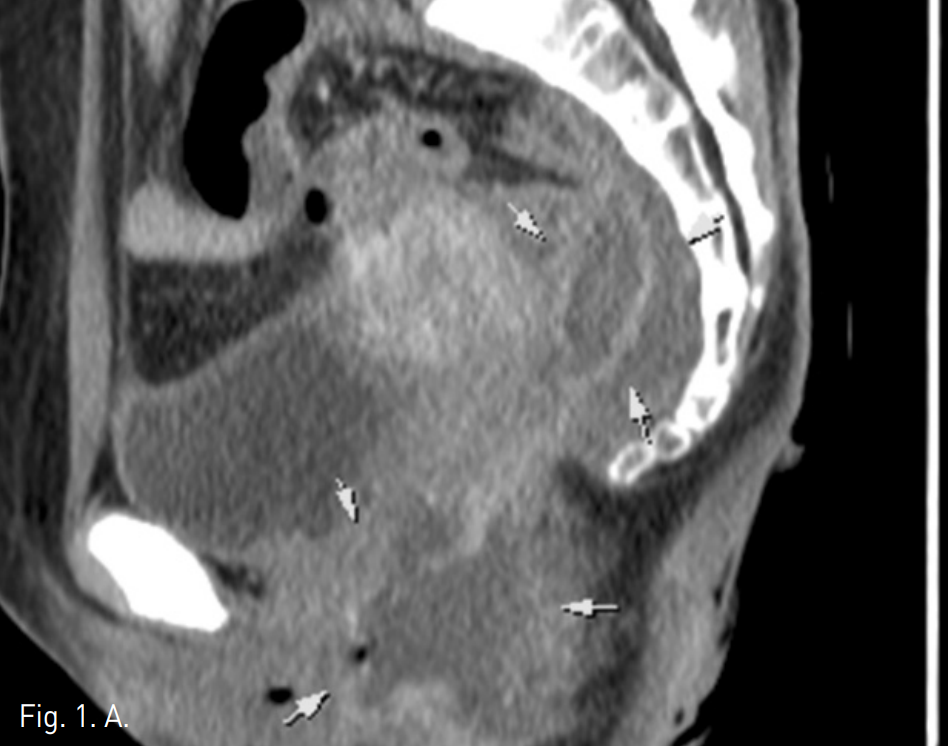

수술 후 15일째 시행한 조영 증강 CT에서 3-5번 천골(sacrum)의 전방으로 약 37x34x15mm크기의 납작한 모양의 액체저류가 관찰되었다. 항문 주변에 45x43x27mm크기의 또 다른 액체저류가 관찰되었다 (Fig. 1).

Fig. 1

A, B. Sagittal (A) and axial (B) CT images show a fluid collection at the presacral space (arrows) above the anastomotic site. Another fluid collection was noted at the perianal area (arrow heads).